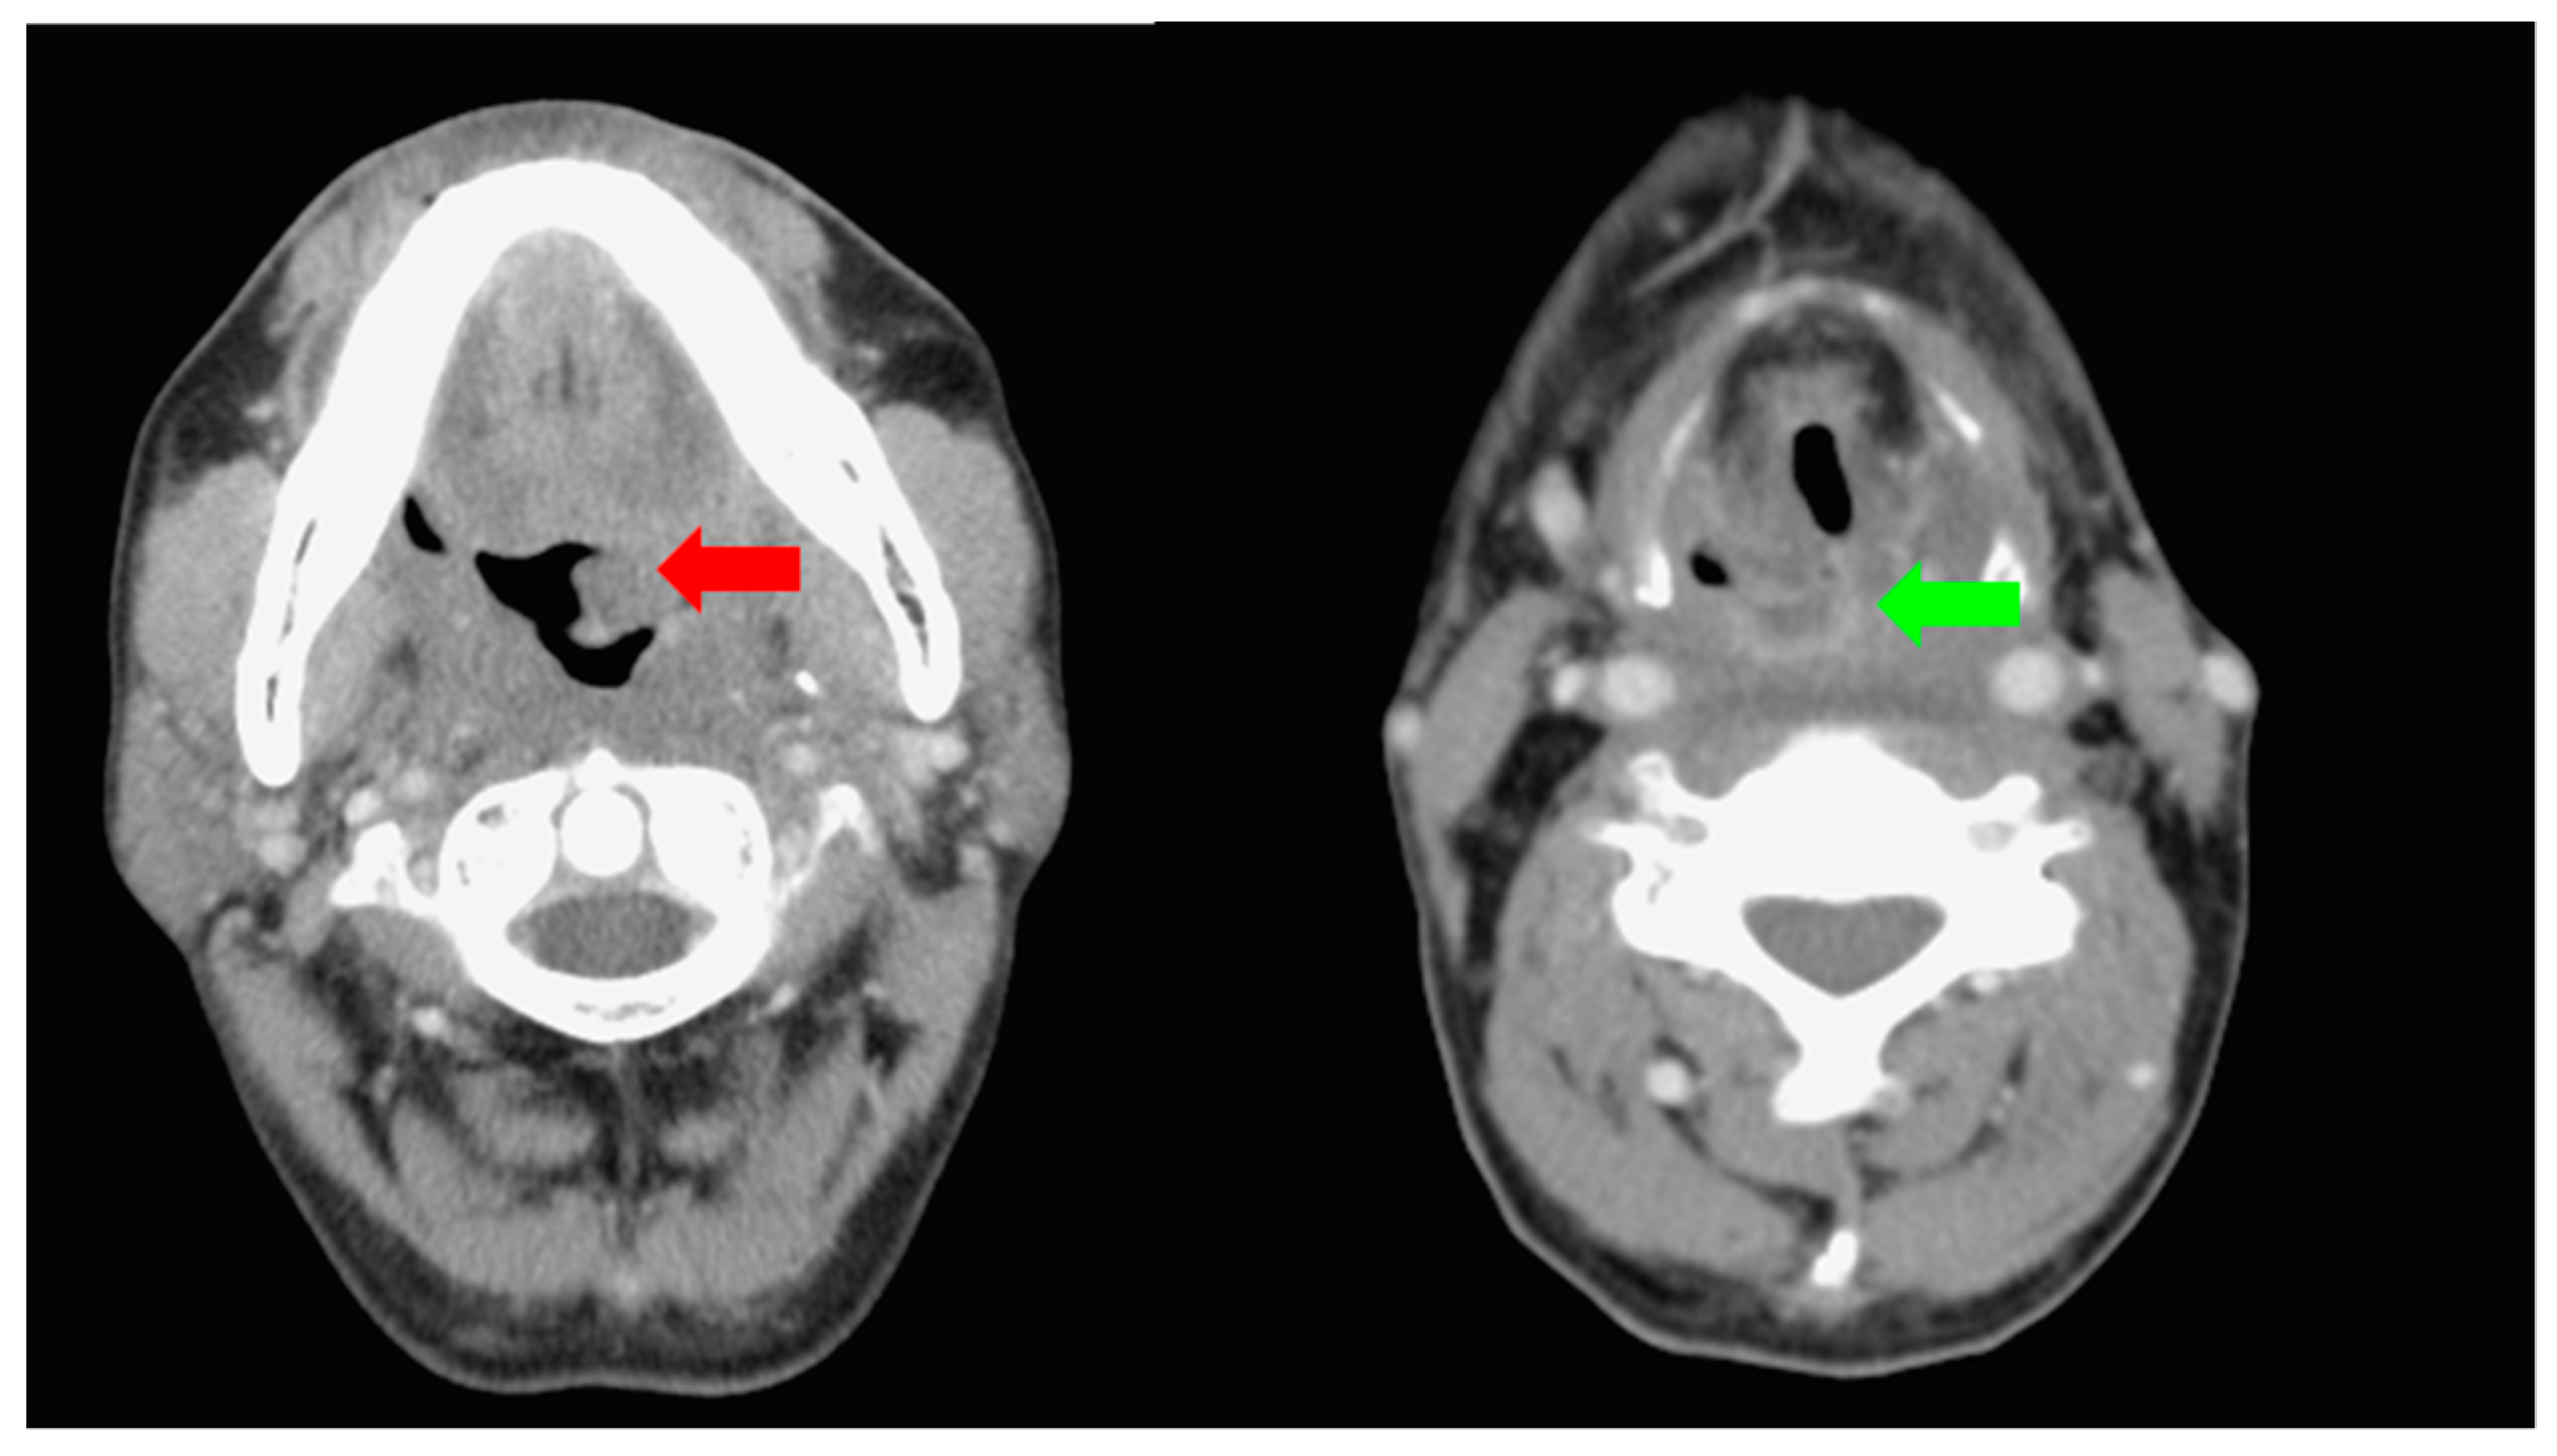

He was admitted to the ward and received further examinations. A computed tomography of the neck showed tumor growth about 2.5 cm in size arising from left aspect of tongue base, and another tumor over posterior pharyngeal wall without obvious neck lymphadenopathy (Figure 2). A computed tomography of the chest, whole body bone scan, and whole body positron emission tomography scan disclosed no distant metastases.

Figure 2.

Computed tomography of neck demonstrating tumor growth about 2.5 cm in size arising from left aspect of tongue base (red arrow), and another tumor over posterior pharyngeal wall (green arrow).